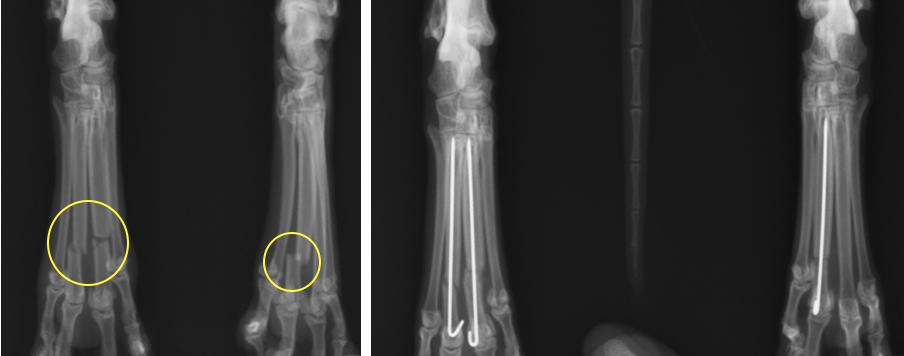

指の骨の骨折(中手骨骨折、中足骨骨折)

指の骨折では人で言う手のひらの骨、つまり中手骨、中足骨の骨折がほとんどです。

猫や小型犬ではピンでの固定が一般的ですが、最近では超小型と呼ばれるプレートスクリューもあるため、2mm程の骨でもプレートスクリューを入れることが可能です。

犬猫では第3指、第4指が重要で、そこの固定をしっかり行わないと足をつくようになりません。

右第3指、第4指の骨折と左第3指の骨折です。それなりに髄腔が広いため太めのピンを入れています。